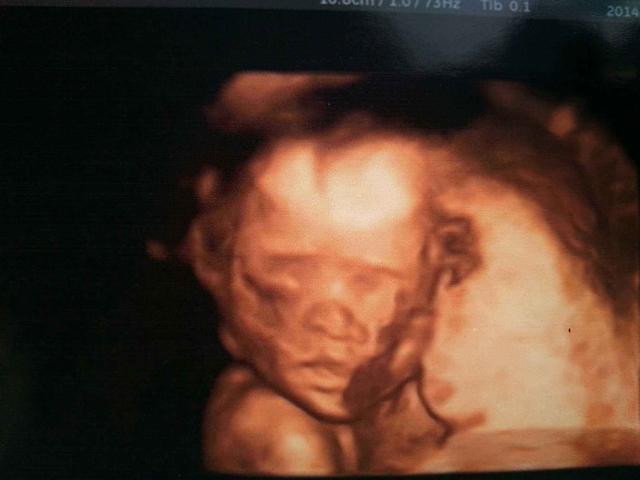

整个孕期检查中,除了NT检查,另一个非常重要的项目就是胎儿大排畸,也就是大家口中的“四维”,这是整个孕期不可忽视的产检项目,准妈妈在这一关都会遇到或多或少的问题,比如胎儿不配合或者胎儿发育轻微异常等等。

四维是使用四维医学彩色超声成像技术,它能够实时获取三维图像,宝妈宝爸们可以看见孩子大体的五官长相。大排畸主要使用三维彩超技术和四维医学彩色超声成像技术,是看不到胎儿的五官的。

注意事项:做胎儿大排畸的时候如果遇到胎儿不配合的情况,准妈妈可以吃些食物或者稍微运动一下,刺激胎儿的胎动,如果胎儿发育指数出现问题,准妈妈要记得及时咨询专业医生。